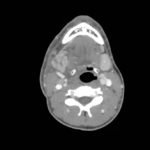

The computed tomography (CT) scan demonstrates prominent enlargement and heterogeneous enhancement of the right submandibular gland (single large arrow) compatible with sialadenitis. There is no evidence of a sialolith or obstruction on the CT. There is associated edema (two small arrows) of the right submandibular space, parapharyngeal space and anterior right neck with partial effacement of the right vallecula and right pyriform sinus.